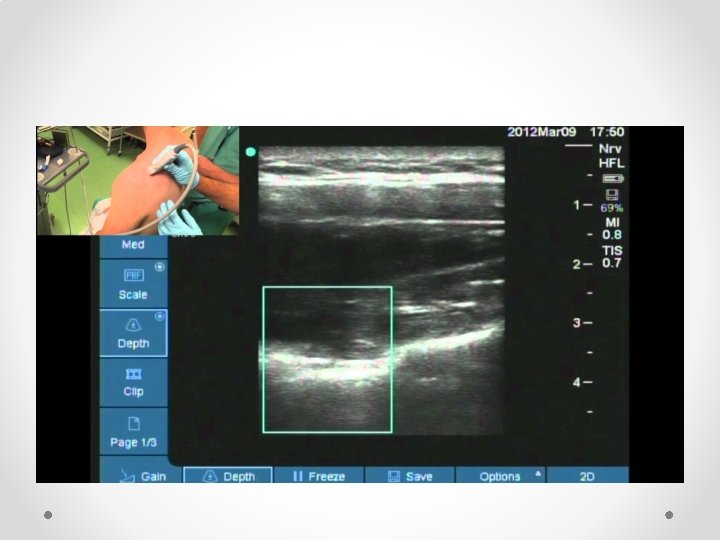

Ultrasound technique • In plane (LEFT) vs out of plane (RIGHT):

In plane vs out of plane • In plane vs out of plane: • I do all my blocks in plane o o Allows you to see both the needle tip and the nerve and ensure no contact With out of plane run risk of spearing the nerve In plane does require more practice to perfect Of needle and ultrasound beam in same plane can see a “false” tip of the needle: giveaway in that will not see the whole needle shaft- if not seeing whole shaft likely that beams aren’t alligned • Only advance the needle when you can see the tip!